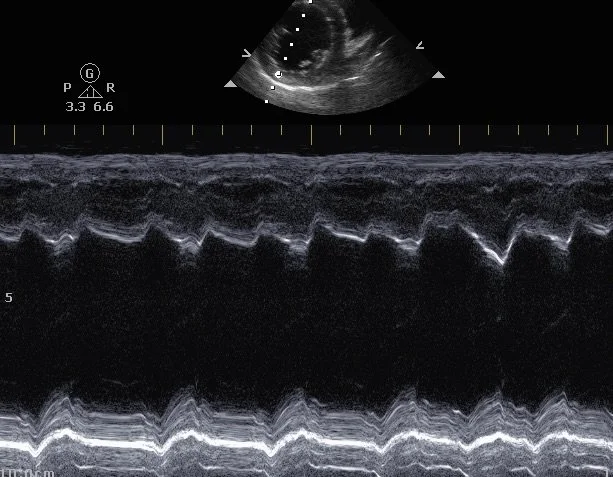

Echocardiography

Echocardiography scan example